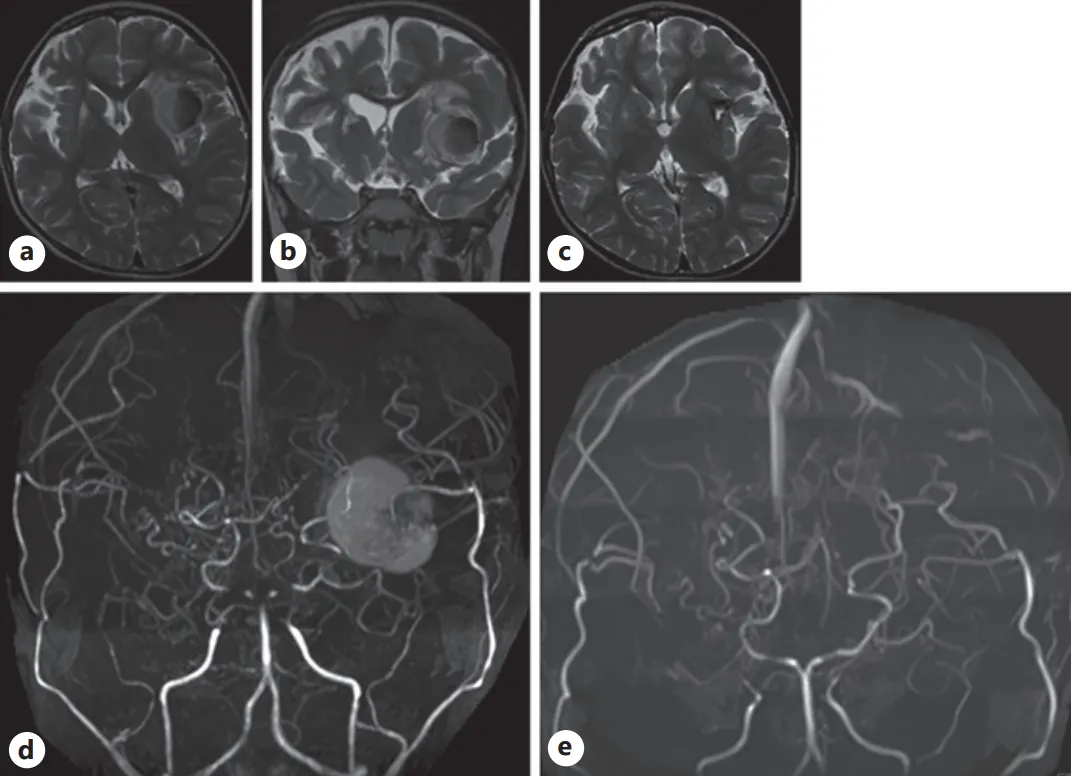

术后随访与新发病灶处理

术后1年半常规MRI复查发现左侧岛叶新发病灶。初期采取保守策略,减少阿司匹林剂量并加强监测。一月后病灶体积增大,虽无临床症状,为预防神经压迫行手术切除。病理检查提示肉芽组织伴反应性胶质增生和毛细血管增生。术后影像学检查证实病灶完全切除,患儿无后遗症发生。